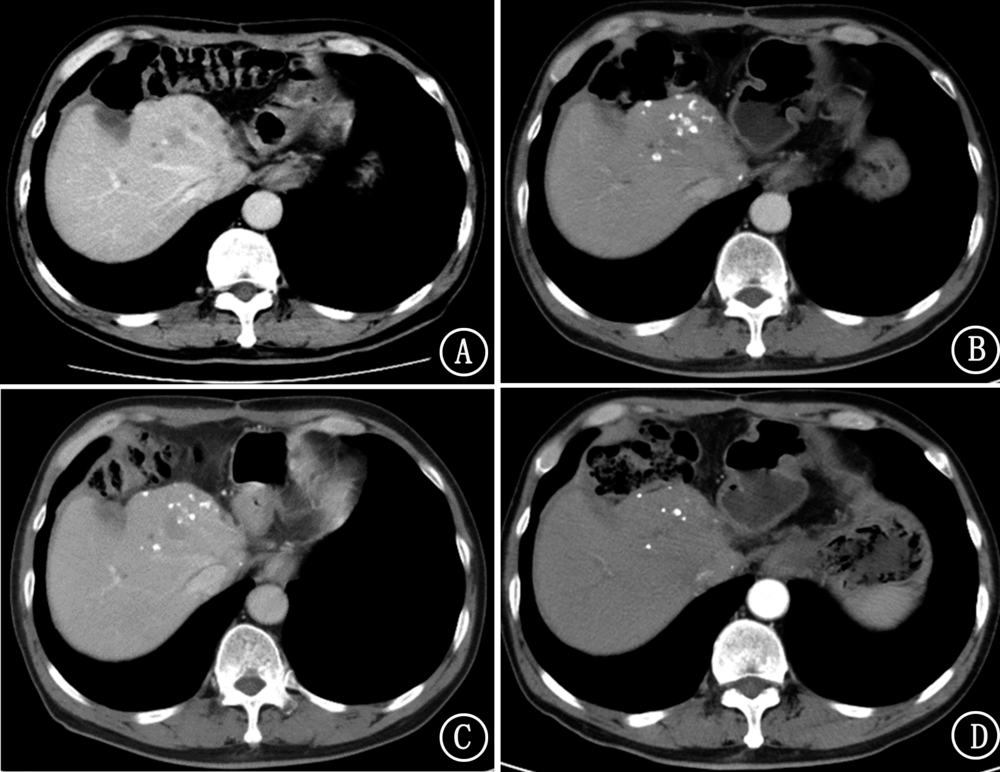

熊敏, 陈翼, 王建波. CT放射组学特征对肺转移瘤的鉴别诊断价值[J]. 国际肿瘤学杂志, 2023, 50(4): 208-213. |